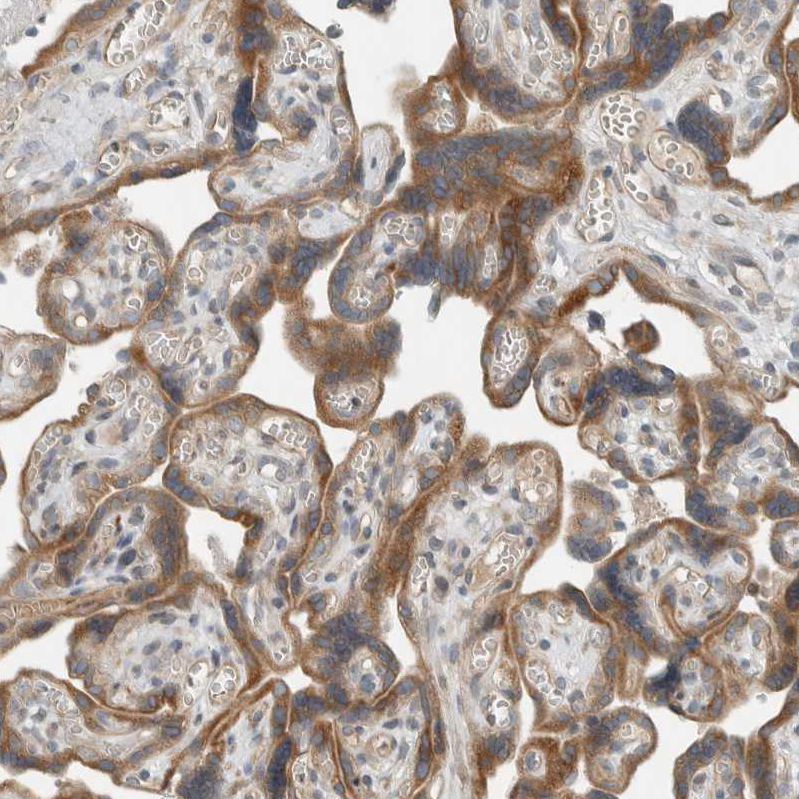

Immunohistochemical staining of human placenta shows moderate cytoplasmic positivity in trophoblastic cells.